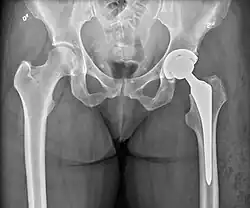

Hemiarthroplasty is a surgical procedure that replaces one half of the joint with an artificial surface and leaves the other part unchanged. This class of procedure is most commonly performed on the hip after an intracapsular fracture of the femur neck (hip fracture). The procedure is performed by removing the head of the femur and replacing it with a metal or composite prosthesis. The most commonly used prosthesis designs are the Austin Moore and Thompson prostheses. A composite of metal and high-density polyethylene that forms two interphases (bipolar prosthesis) can be used. The monopolar prosthesis has not been shown to offer any advantage over bipolar designs. The procedure is recommended only for elderly/frail patients, due to their lower life expectancy and activity level. This is because over time the prosthesis tends to loosen or to erode the acetabulum.[101] Independently mobile older adults with hip fractures may benefit from a total hip replacement instead of hemiarthroplasty.[102]

X-ray of the hips, with a right-sided hemiarthroplasty